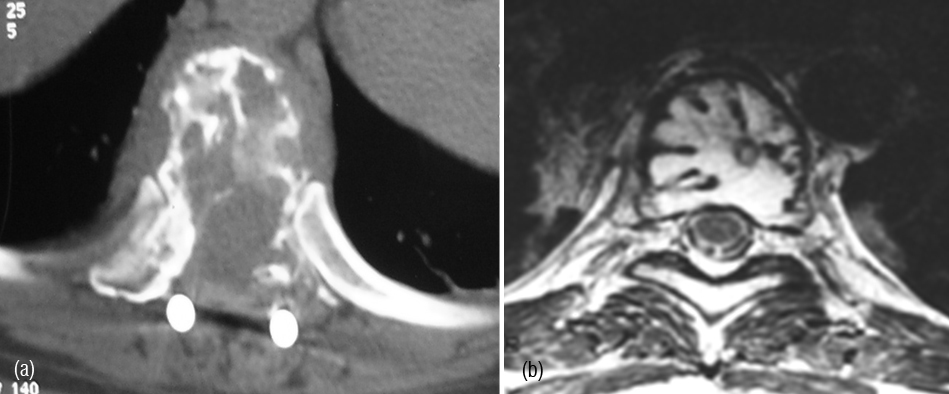

CT and MRI demonstrate lytic areas with struts of bone interspersed. In MRI, plasmacytoma shows a classical minibrain appearance (Figure 4abc). At times, it is difficult to differentiate hemangioma from plasmacytoma (Figure 5ab). It may remain localized for many years but more than 30% progress quite rapidly to generalized myelomatosis with a latent interval of 5-10 years. Radiological features are listed in table 1.

Figure 4a,b,c: CT - Plasmacytoma of sacrum, an expanding lytic lesion.

Figure 5: (a) CT (post op.), (b) MRI – Minibrain appearance